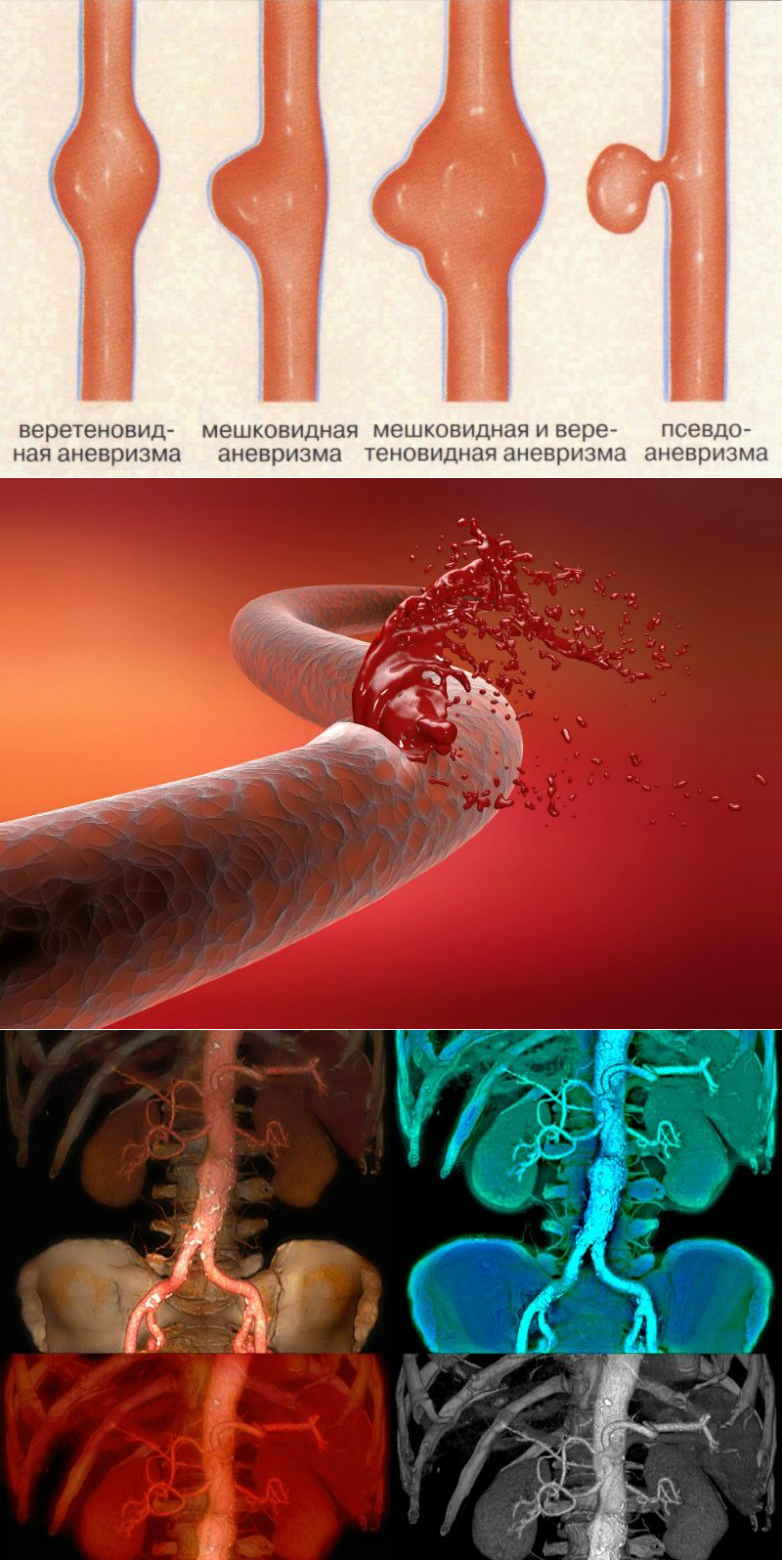

Снимки и иллюстрации микроаневризм сосудов головного мозга